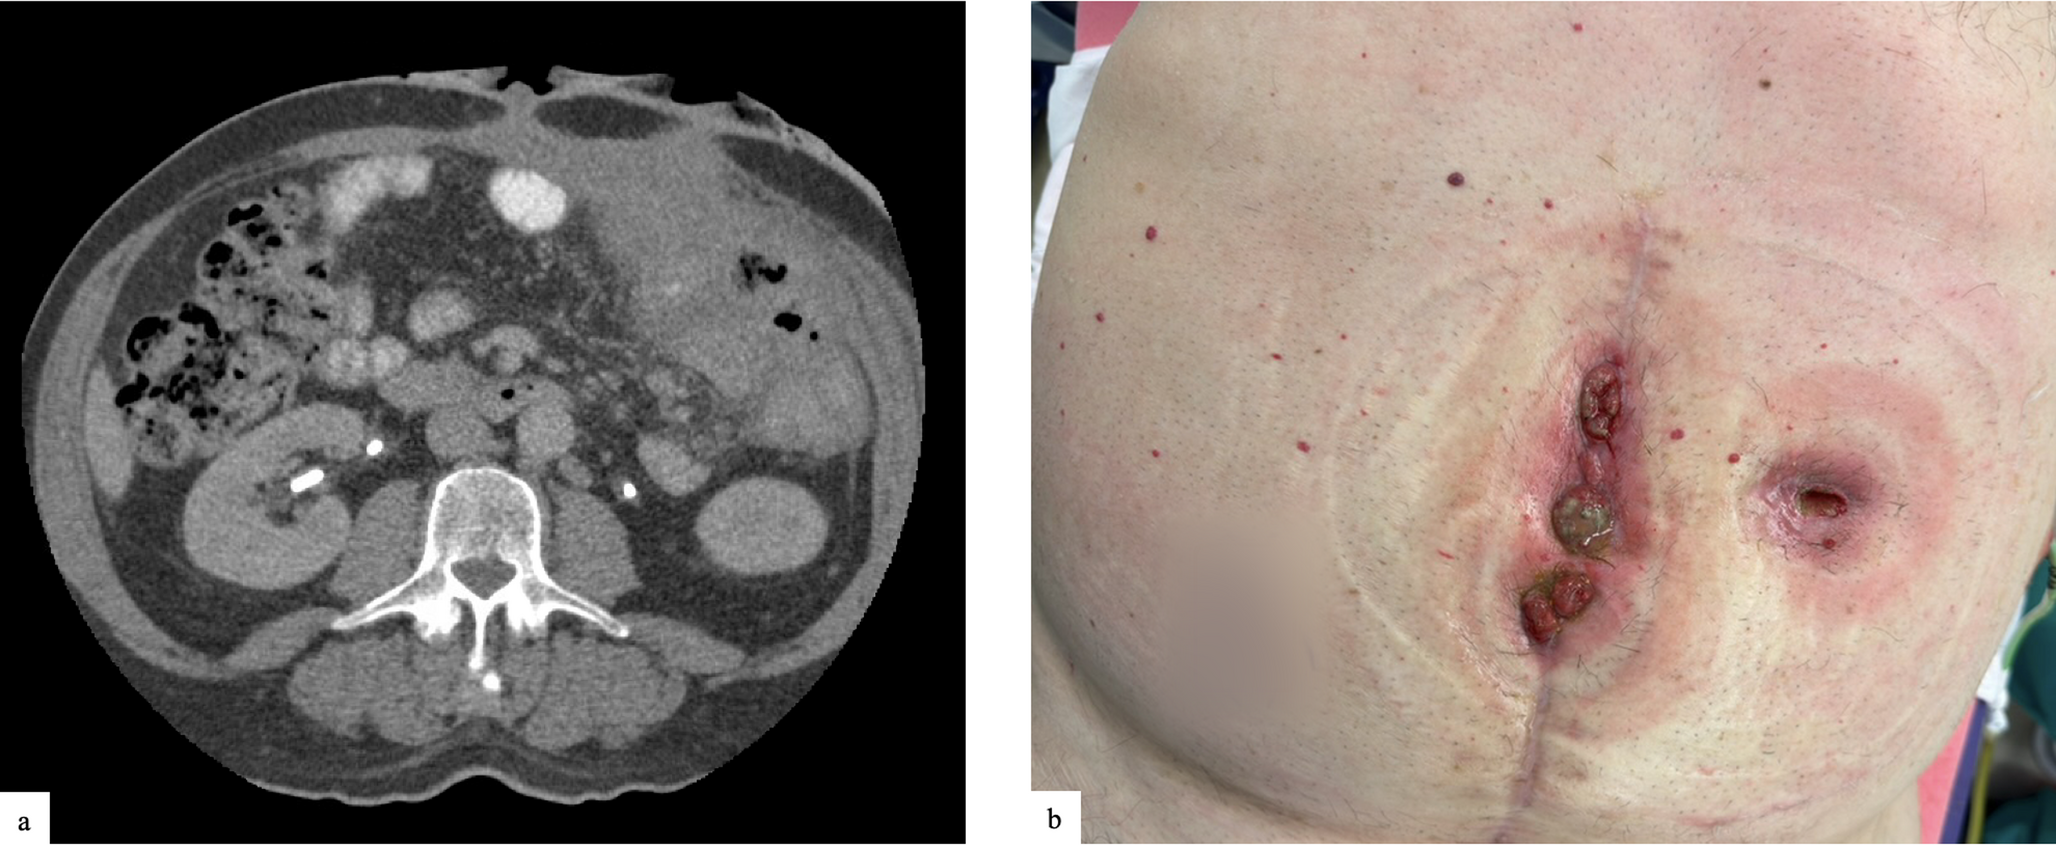

Fig. 2

shows a 60-year-old man with a history of Crohn’s disease and multiple enterocutaneous fistulae presenting for fistula takedown, incisional hernia repair and ostomy reversal, (a) shows the preoperative axial CT scan with evidence of multiple fistula and significant hernia (b) preoperative clinical photographs of wounds

Bild vergrößern